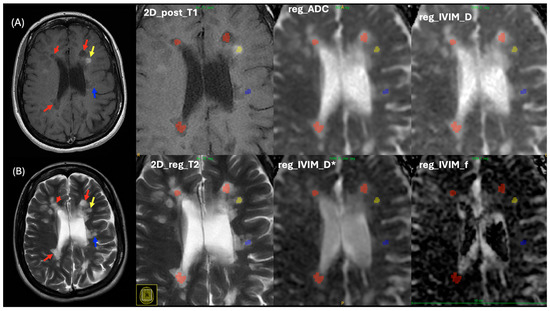

2.2. Lesion Analysis

2.3. MRI Imaging Protocols

2.4. MRI Processing